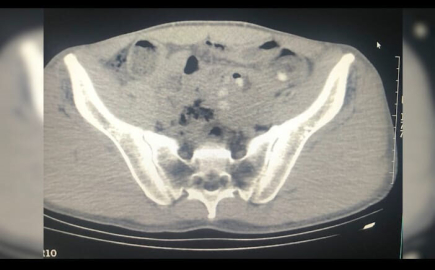

İl Emniyet Müdürlüğü Narkotik Suçlarla Mücadele Şubesi ekipleri, Tatvan ilçesindeki uygulama noktasında yol kontrolü sırasında bir yolcu otobüsünü durdurup, arama yaptı. Ekipler, şüpheli hareketleriyle dikkat çeken yabancı uyruklu 3 kişinin sırt çantalarında yaptığı aramada 109 parça halinde metamfetamin ele geçirildi. Gözaltına alınıp hastaneye götürülün şüphelilerin çekilen röntgenlerinde de midelerinde 45 kapsül metamfetamin tespit edildi. Şüphelilerin midesindeki uyuşturucu doğal yollarla çıkarıldı.